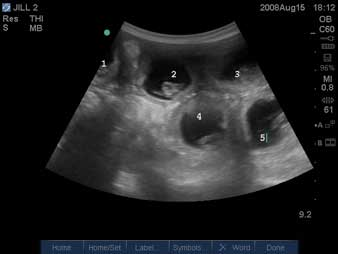

Attēlā redzam ar ultrasonogrāfijas metodi iegūtu kaķenes dzemdes attēlu - tajā attīstās pieci kaķēni.